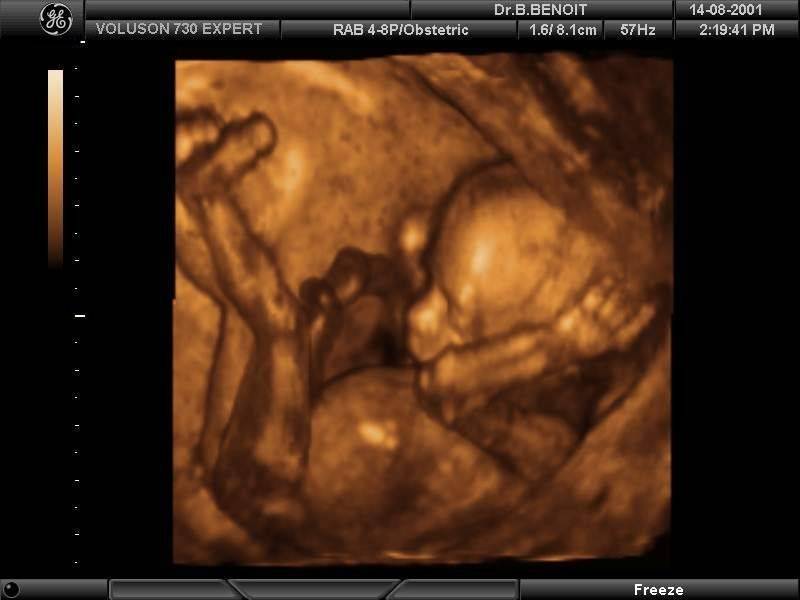

- 3D ультразвуковое исследование;

- И даже 4D УЗИ.

3D УЗИ – это уникальнейшее исследование (показывает ребенка в трехмерной плоскости), благодаря которому, женщины могут увидеть не просто облик своего малыша, а рассмотреть его крохотные пальчики, глазки, в какой позе он находится. Этот вид ультразвукового исследования также безопасен, как и обычный, но он имеет намного больше плюсов. С помощью 3D можно легко развеять сомнения, есть или нет нарушения, патологии или пороки у плода.

Если первое УЗИ, которое проводят на 13-14 недели беременности делают обычное, то начиная с 16-й недели можно делать 3D-ультразвуковое исследование. Если во время первого исследования будущего ребенка еще называли эмбрионом, то на 16-й неделе его можно назвать человечком, так как уже сформированы все наружные части тела.

4D-УЗИ такое же, как и 3D. Единственная между ними разница – это четвертое измерение – время. При 3D-ультразвуковом исследовании вы получаете лишь картинку малыша, а при 4D – видео, где можно увидеть как он шевелится.

Трехмерная ультразвуковая диагностика — это ультразвуковое исследование, в результате которого можно получить изображение или даже видео еще не родившегося ребенка. А вот что касается поведения данного обследования, то тут есть несколько аспектов, как этических, так и с точки зрения безопасности.

После проведения обследования можно получить снимки УЗИ мальчика или девочки и это будут их самые первые фото. А вот при 4D УЗИ можно даже получить первую видеозапись. Однако подобной функцией обладают и обычные аппараты УЗИ, но не все.